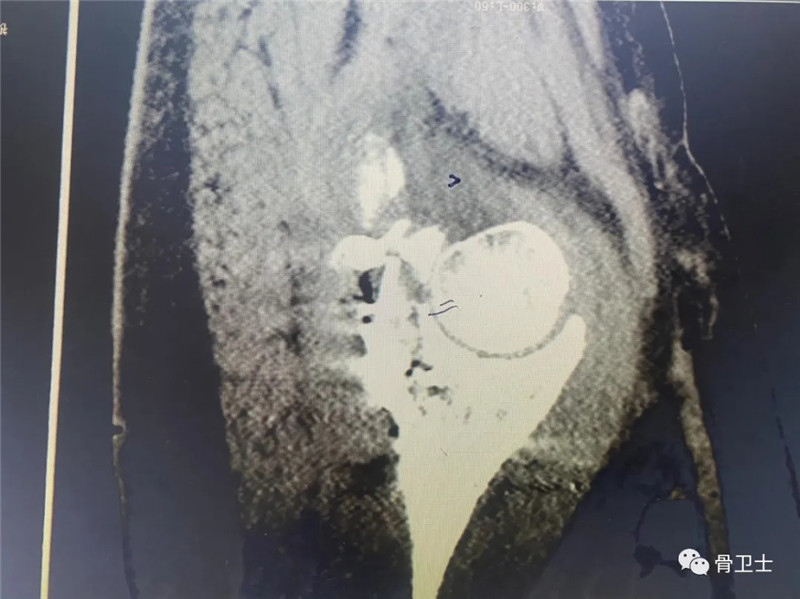

辅助检查:完善血型0型,Rh(D)血型阳性。2月22日,血常规示白细胞15.11X10^9/L、中性细胞比率90.51%,血象偏高,考虑创伤后体内应激反应所致;电解质常规检查:钾5.74mmol/L,嘱其低钾饮食,择期复查;肝功能常规:谷草转氨酶65U/L,考虑创伤所致,择期复查;血糖11. 82mmol/L,为餐后血糖,实属正常。新冠肺炎检查、肾功能示未见明显异常。心电图示窦性心动过速,电轴正常;头颅+胸部CT示未见明显外伤性异常;左髋关节正侧位片+左膝关节正侧位片示左髋臼粉碎性骨折,左股骨头脱位;左髋关节正侧位片+左膝关节正侧位片示左髋臼粉碎性骨折,左股骨头脱位;CT成套:双髋关节(CT重建):左侧可见粉碎性骨折、股骨头后脱位。

术后影像: